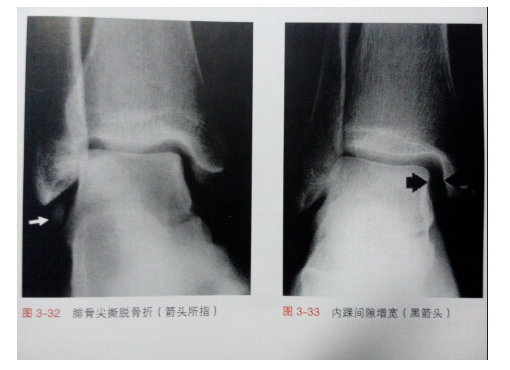

踝关节不稳定

X线片检查

- 常规行正位、侧位、踝穴位

- 特殊位置:节内旋位、内斜位

- 应力位:前抽屉应力、距骨倾斜应力